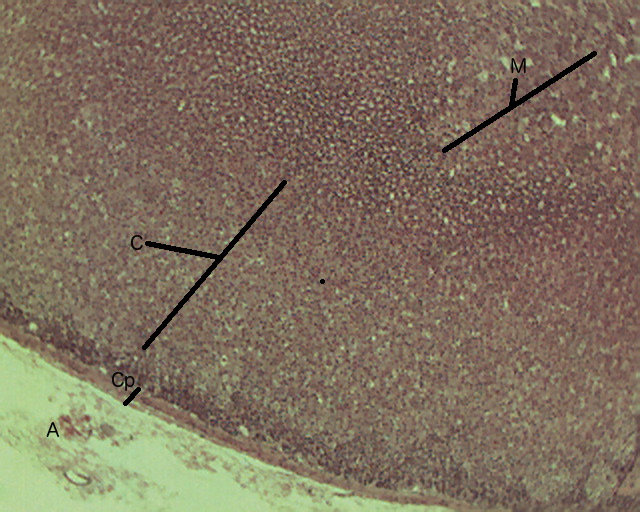

Adrenal Gland Tutorial Histology Atlas for Anatomy and Physiology

Adrenal Gland, 4X, labeled Histology Adrenal Gland Tissues Veins and lymphatics leave each gland via the hilum, but arteries and nerves enter the. The adrenal gland consists of an outer cortex of glandular tissue and an inner medulla of nervous tissue. The adrenal glands consist of an outer connective tissue capsule, a cortex and a medulla. The adrenal gland comprises 2 distinct tissues: The cortex itself is divided. Adrenal Gland Tissues.